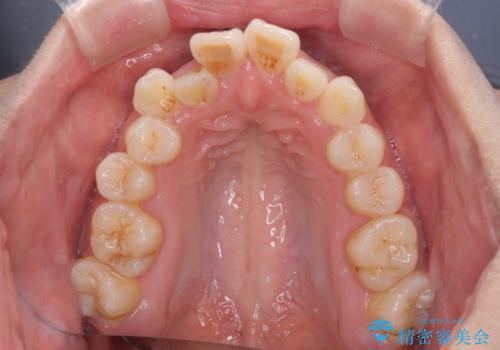

- 前歯の開咬と、上顎前歯の八重歯やデコボコを気にして来院された患者様です。

上顎歯列が狭窄していたため、急速拡大装置により上顎骨を側方に拡大し、その後ワイヤー装置にて矯正治療を行うこととしました。

上顎骨を拡大することで、八重歯やデコボコを歯列に収めることができ、下顎の歯が外に位置していた奥歯の咬み合わせも改善することができました。